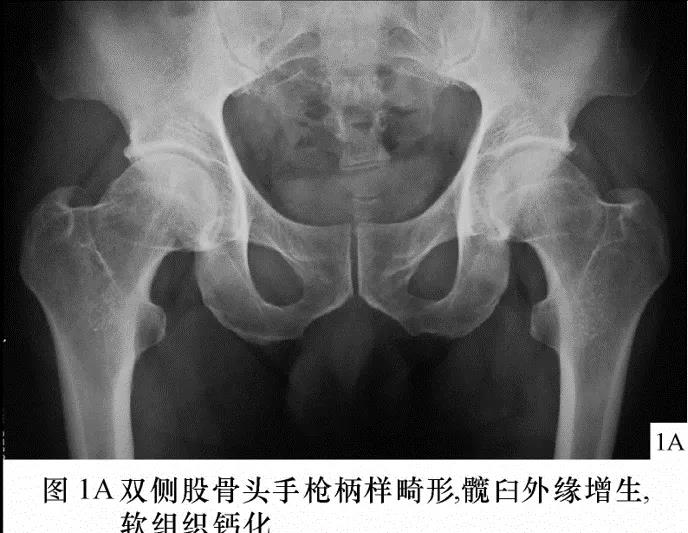

FAI影像学检查前后位片:可见股骨头不同程度的手枪柄样畸形侧位片: 观股骨头颈交界处骨性隆起;CE角﹥40°;髋臼后倾畸形;股骨颈的囊性变

FAI:齿轮型(cam-type )影像:股骨头、颈间的凹陷不足,可伴局部的骨质增生、硬化、囊变部位:前外股骨头、颈交界区